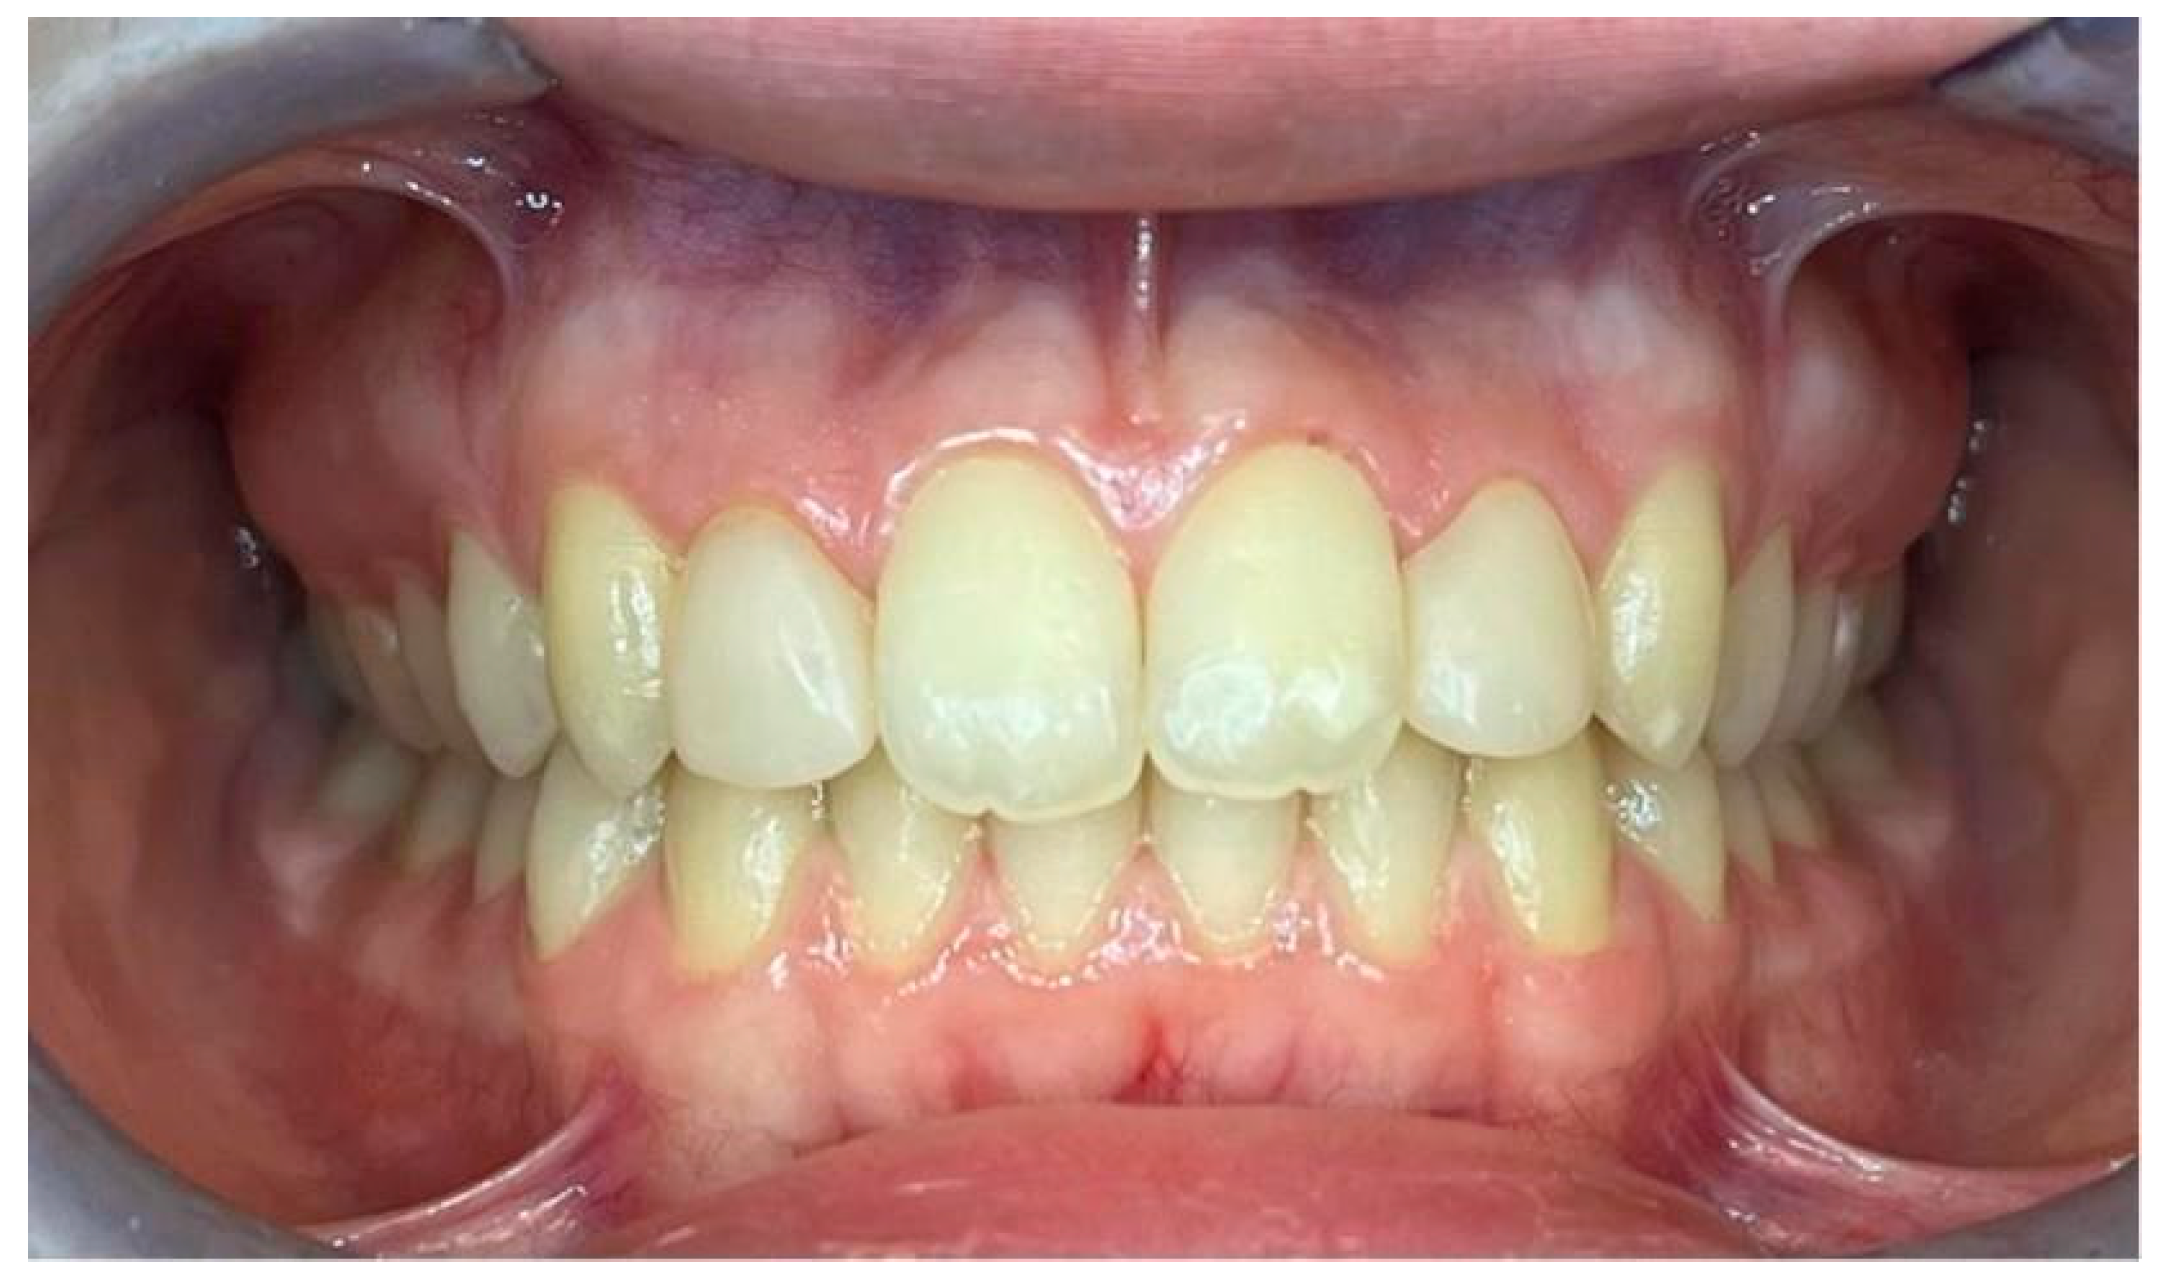

A 12.3-year-old male patient presented for an orthodontic consultation due to dissatisfaction with the aesthetic appearance of his smile. Clinical examination revealed small lateral incisors that were not prominent and unerupted canines (teeth 13 and 23) (Figure 7).

Figure 7.

(a) Frontal view of the dental occlusion in maximal intercuspation. (b) Detailed dental anomalies of teeth 12 and 22.

2.2.2. Clinical Findings

The patient exhibited a skeletal Class I relationship with a tendency toward Class III and an oval facial form characterised by symmetrical proportions and a convex profile—the molar and canine relationships aligned in a Class I configuration with harmonious midline alignment (Figure 7). Dental arches displayed spacing without crowding, and no carious lesions were observed in the anterior or posterior regions.